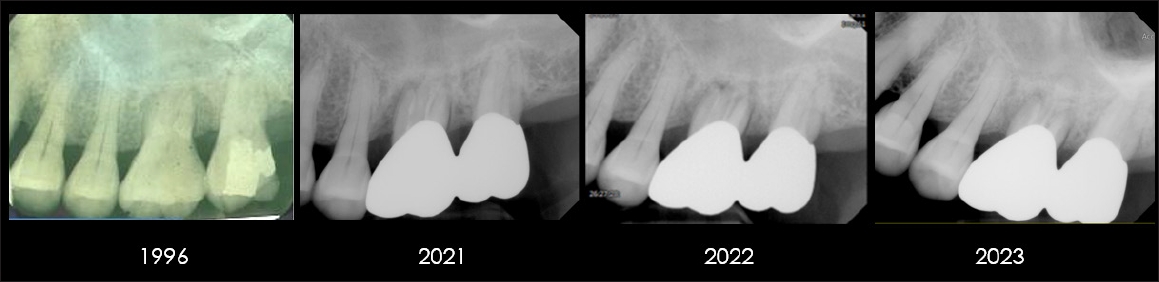

A 41-year-old female was referred in 2008 from the hospital for evaluation and management of generalized Stage III (severe) periodontitis. She had previously been advised of the potential need for multiple extractions and guided bone regeneration prior to implant placement. At baseline, periapical radiography revealed severe generalized alveolar bone loss and pronounced tooth mobility (Fig. 3). The patient’s medical history was non-contributory, with no evidence of systemic conditions such as diabetes or cardiovascular disease. Socially, she was employed in a stable position and reported no psychosocial factors that could interfere with treatment compliance.

Full-mouth periapical radiograph at baseline (2008), showing generalized severe alveolar bone loss and advanced periodontal destruction

Initial non-surgical periodontal therapy consisted of two visits of SRP, supplemented with systemic doxycycline (100 mg daily for 2 weeks). At the 4-month re-evaluation, gingival recession was evident, whereas the initial findings of redness, swelling, and bleeding on probing had resolved. Radiographs demonstrated a well-defined cortical margin and stable horizontal alveolar bone levels following subgingival calculus removal (Figs. 4 and 5).